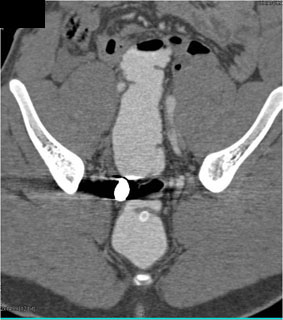

In this patient with a gunshot to the pelvis contrast was placed in rectum and demonstrated

rectal perforation